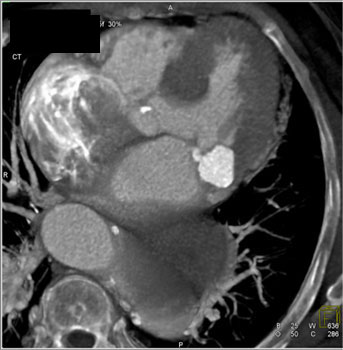

![]() | Question 3: 87 yr old female with history of hypertension had negative stress echo, presents with acute chest pain. What’s the diagnosis? |